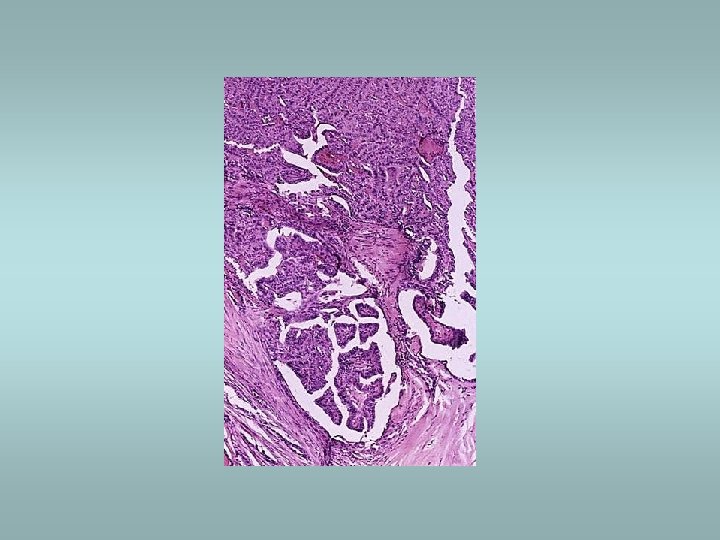

Tumors Benign – adenomas ü Well demarcated ü Fibrosis ü Haemorrhage ü Calcifications ü Hürtle cell adenoma - oncocytic ü Usually „cold“ Malignant - carcinomas ü See transparency